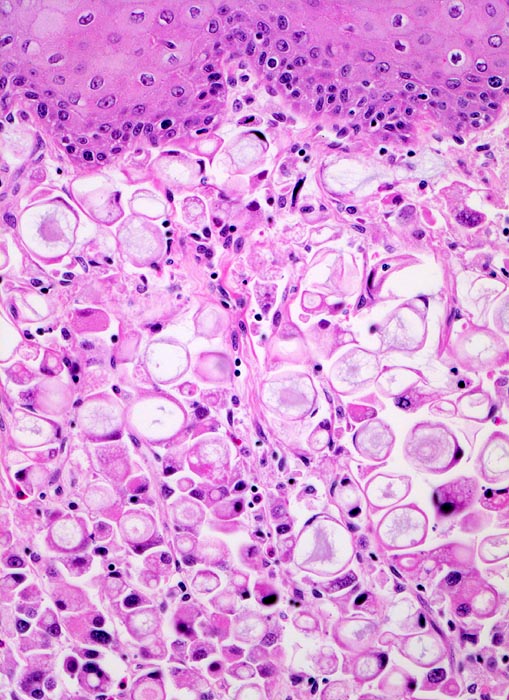

PathoPic – image database / PathoPic ID 3321 - Siegelringzellkarzinom des Magens: Tumorinfiltration des Ösophagus

Siegelringzellkarzinom des Magens: Tumorinfiltration des Ösophagus

Der Tumor breitet sich submukös im Ösophagus aus. Die Ösophagusschleimhaut über dem Tumor ist intakt. Der Tumor besteht praktisch ausschliesslich aus Siegelringzellen mit unterschiedlich grossen Schleimvakuolen, die den Kern zur Seite drängen.

Magenkarzinome, die zu mindestens 50% aus Siegelringzellen bestehen, werden gemäss WHO als Siegelringzellkarzinome bezeichnet.